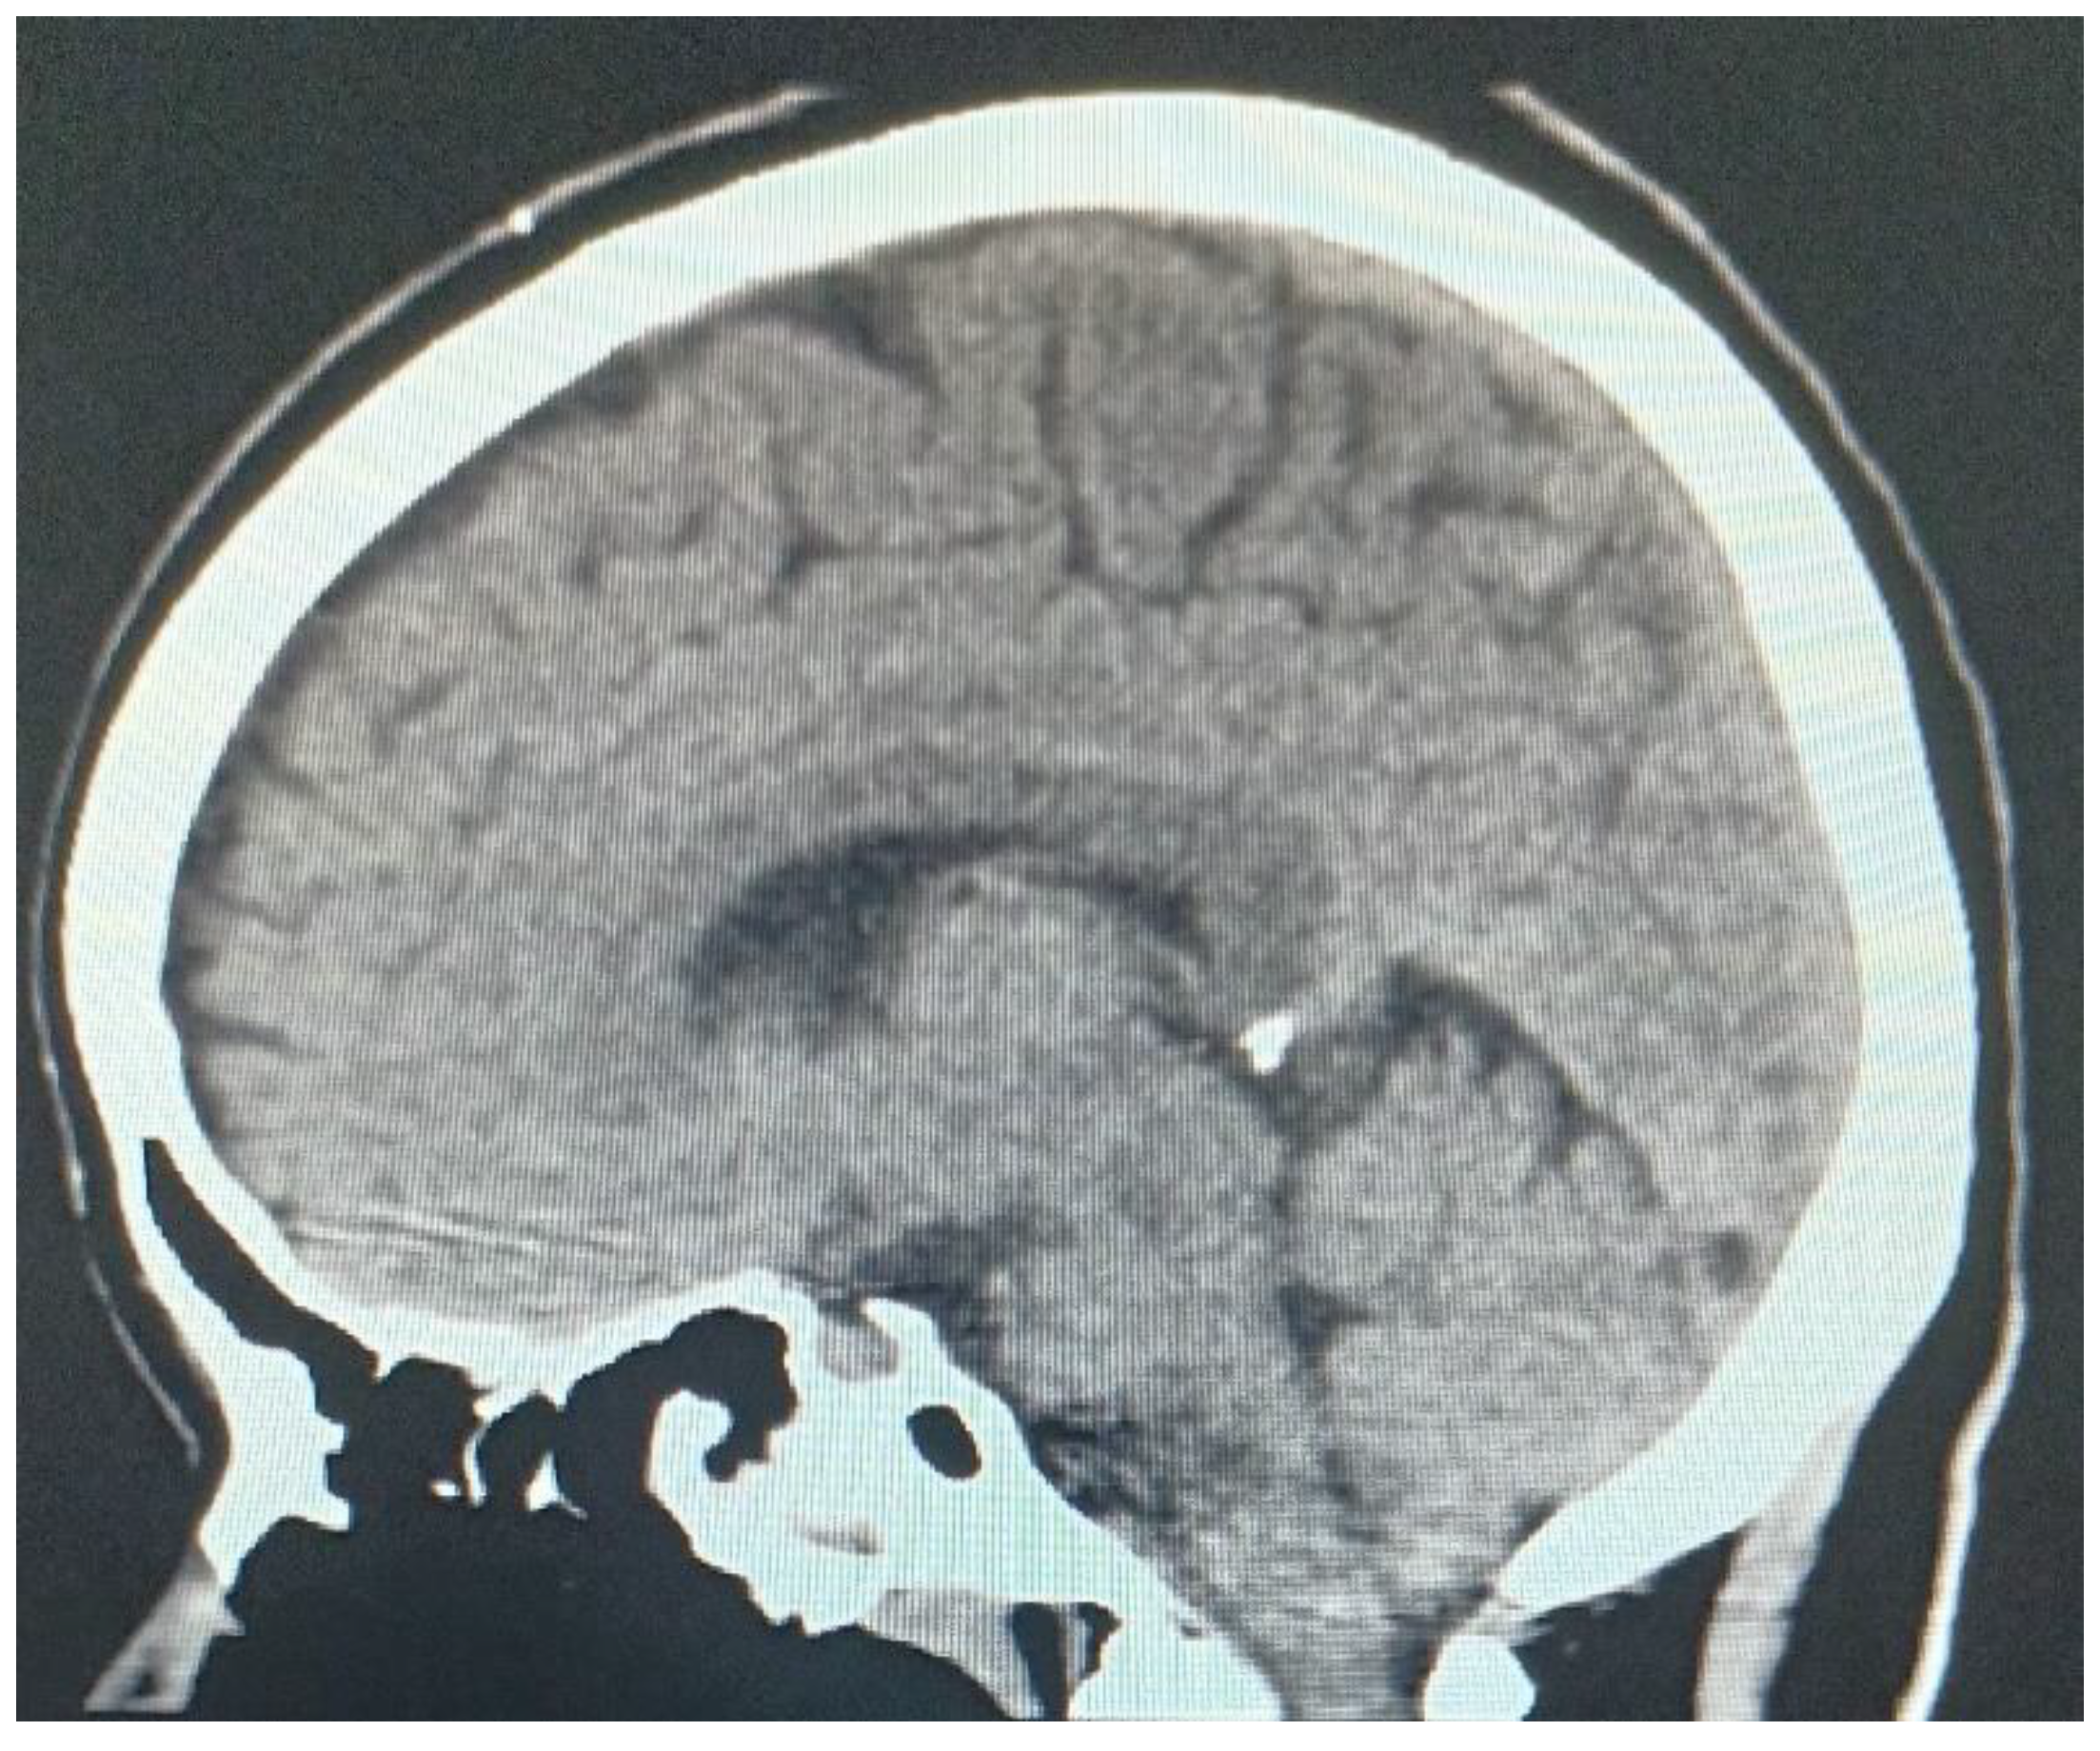

Simple and contrast-enhanced computed tomography is an examination that can help in the diagnosis in the acute phase between a hemorrhagic or ischemic vascular lesion (Figure 1).

Figure 1. Combination of pontine and bulbar petechial hemorrhages with lower pontine infarction in a patient with mild head injury.